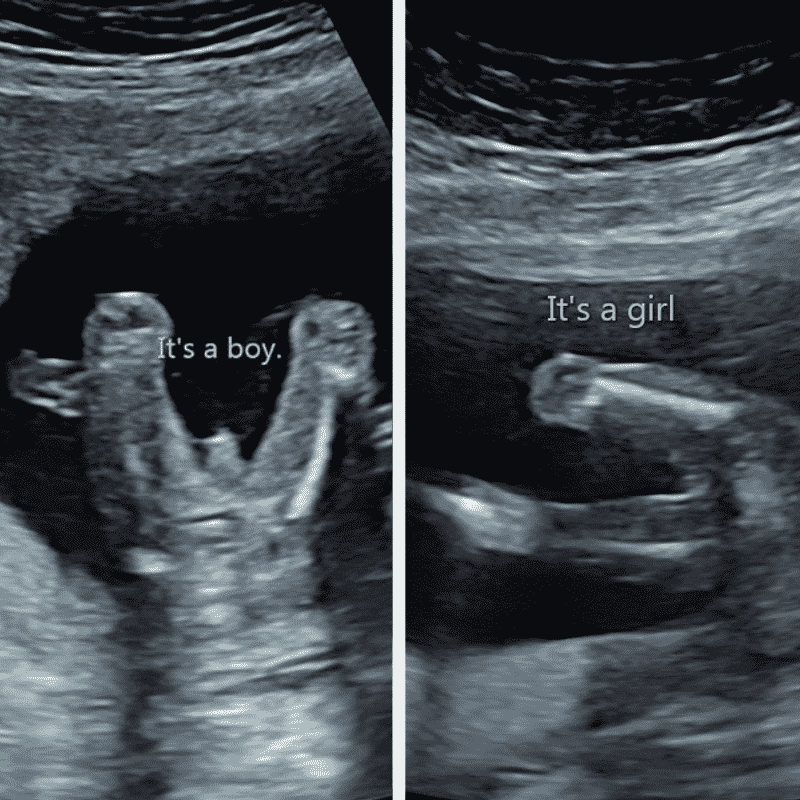

The baby’s nub is its’ genital tube (a penis like stump) between the legs where genitals will eventually develop. The theory states that if the nub points up at 30 degrees or more – you’re having a boy and for a girl it’s almost straight. In order to have the best chance of predicting babies gender, the baby must not be curled up, kicking or lying at an awkward angle. You want them lying nice and flat on their side or else there’s a chance you can’t see the important bits!

Below are ultrasound scans of slightly later stage babies. You can see the ‘boy genitalia’ on the left picture, and the renowned ‘three white lines’ on the right – a key indicator that you’re expecting a girl.